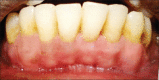

Gingival recession is defined as the apical migration of the gingival margin with exposure of root surfaces. The etiology of the condition is multifactorial. Given the high rate of gingival recession defects among the general population, it is imperative that dental practitioners have an understanding of the etiology, complications and management of the condition. A recent innovation in dentistry is the preparation and use of platelet-rich fibrin (PRF) for recession defects. The article presents a case report, which highlights the use of lateral sliding bridge flap along with PRF in a collagen membrane carrier (guided tissue regeneration) for the treatment of multiple recession defects.